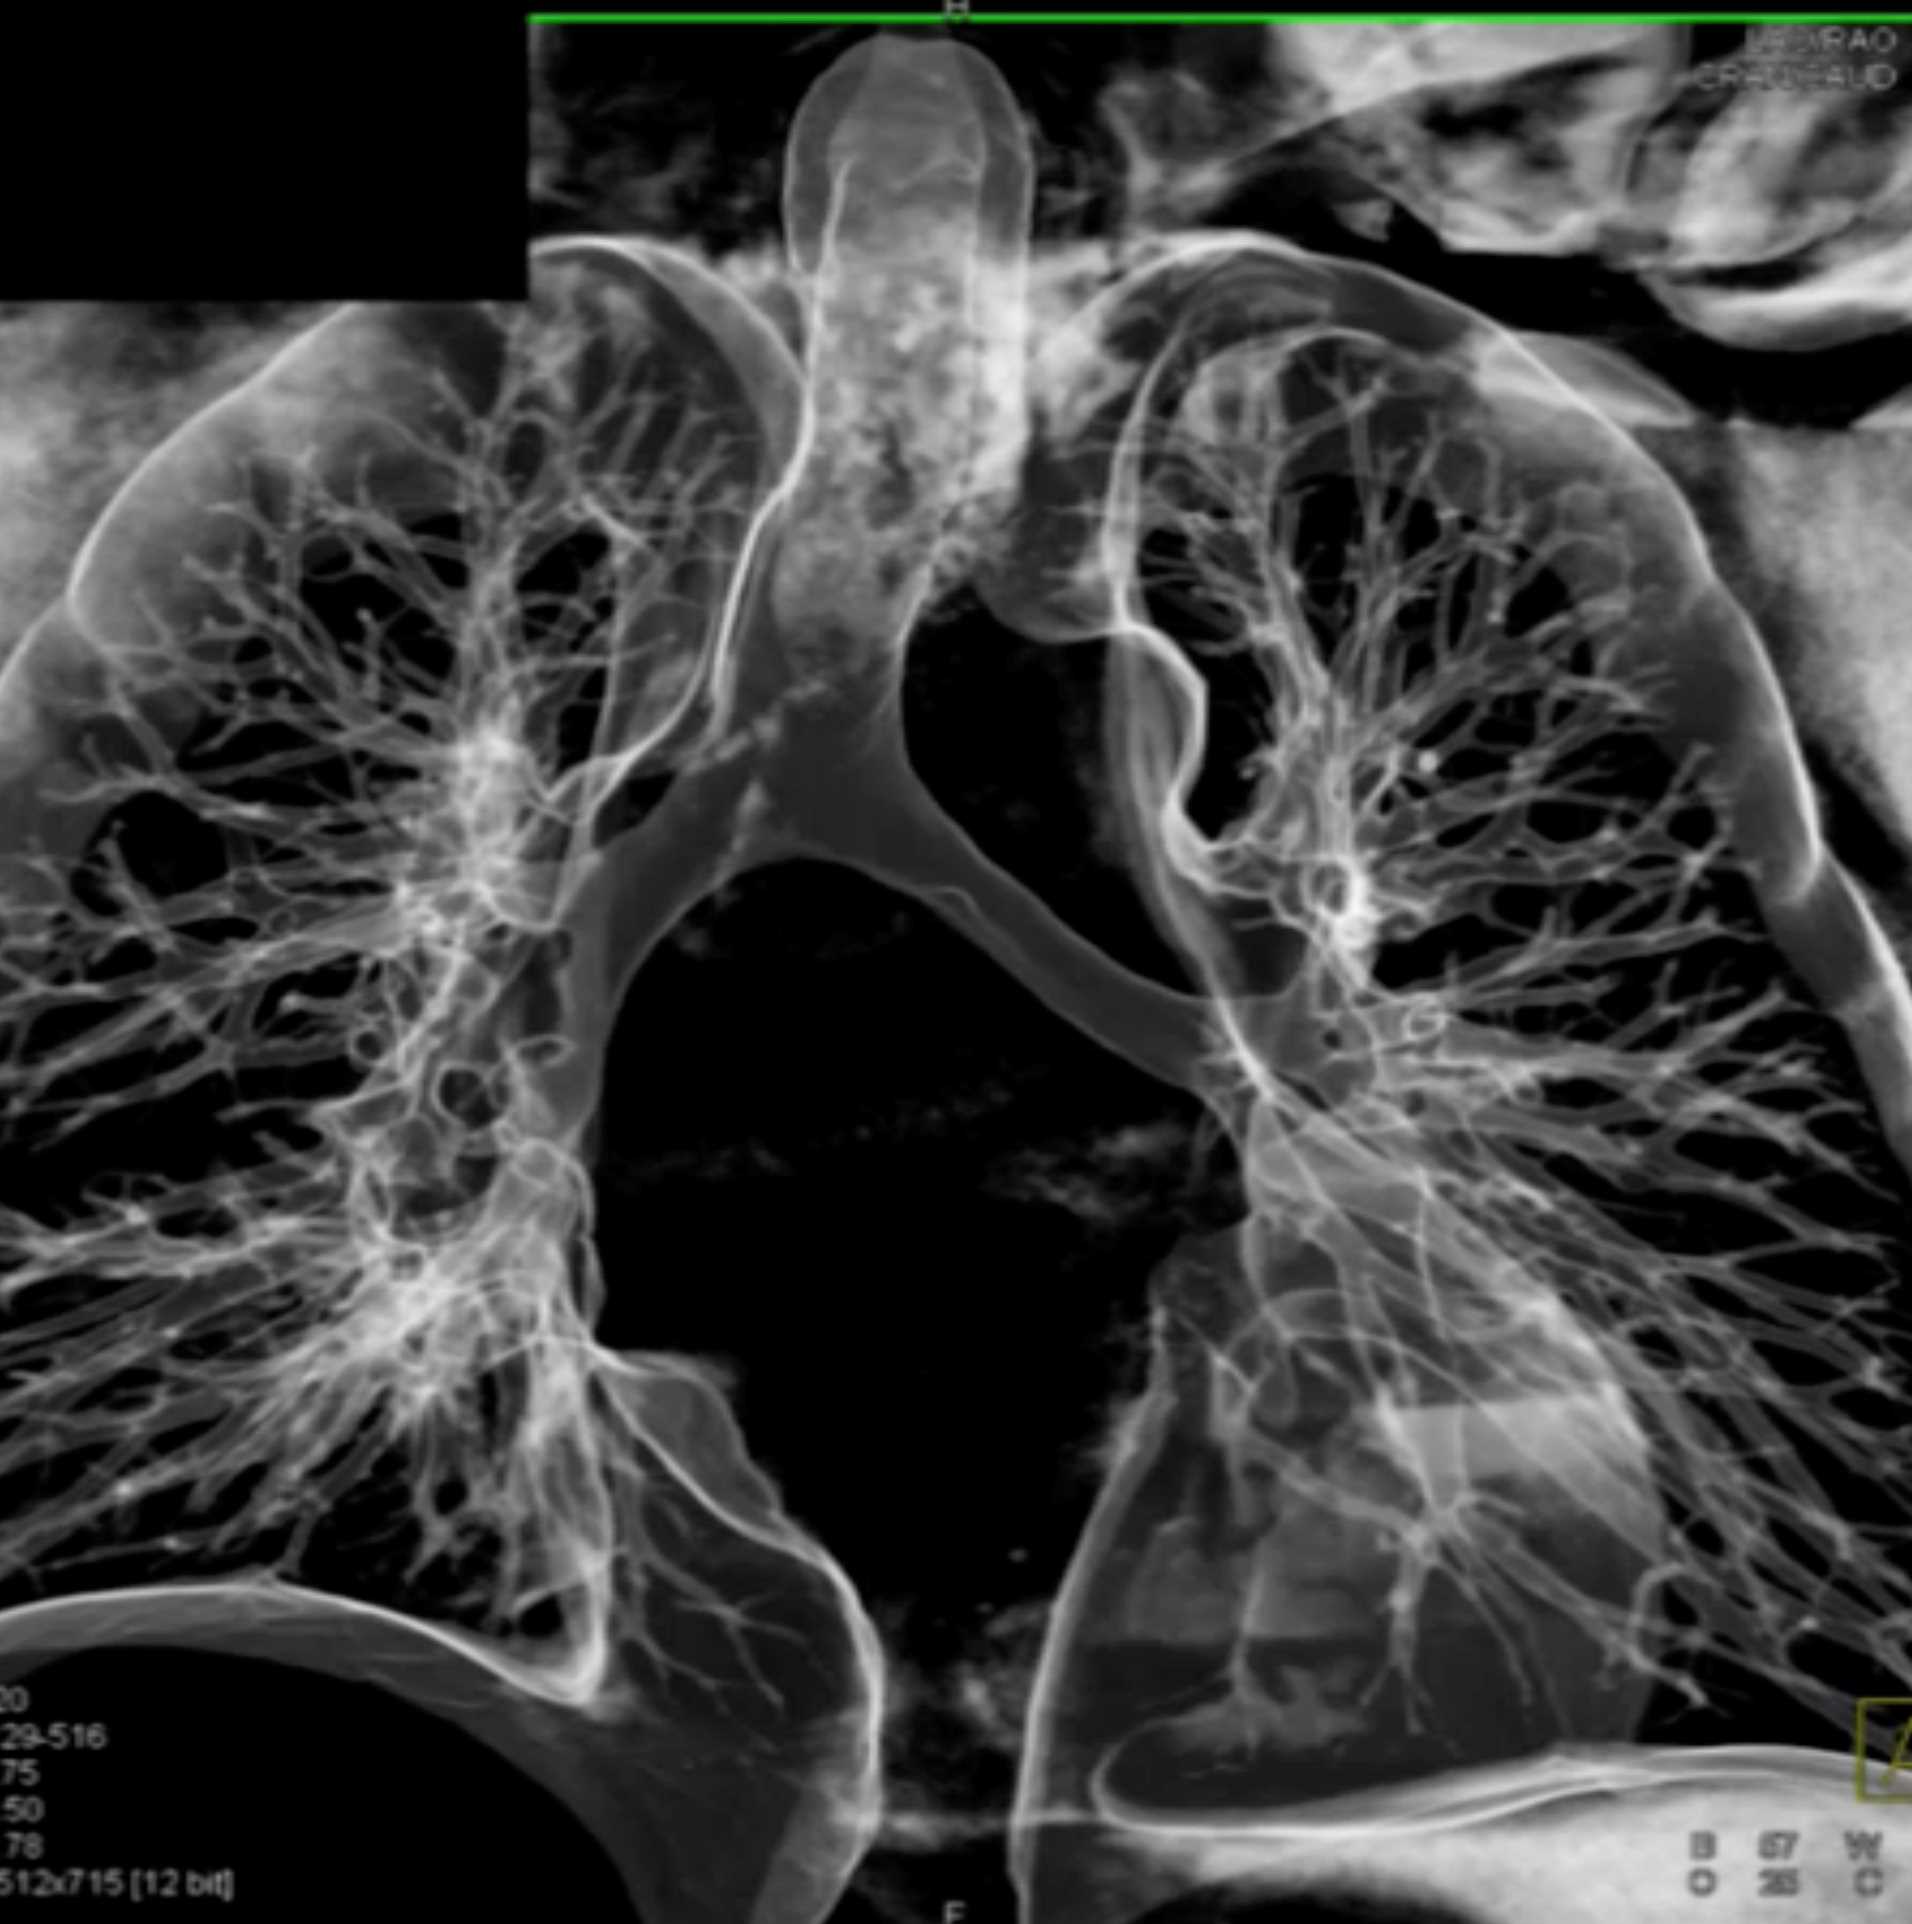

Fibrosing Mediastinitis